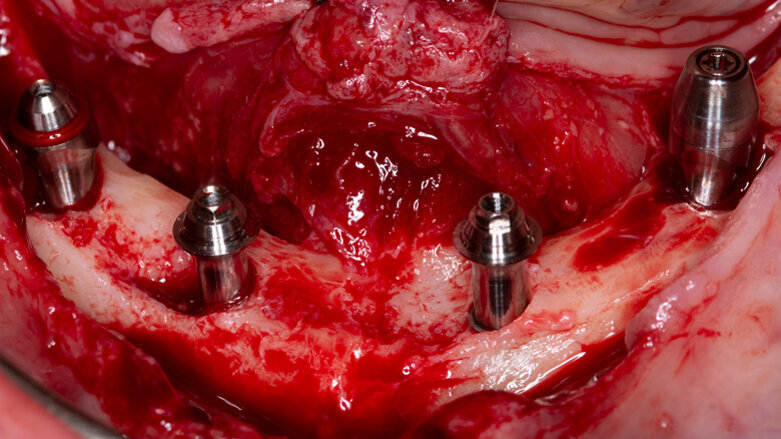

Un paziente di sesso maschile di 44 anni giunge alla nostra clinica privata dopo essere stato inviato da una collega dentista per la valutazione del caso e la proposta di un piano di trattamento. Il paziente riferisce di vivere una situazione di estremo malessere a causa delle condizioni della sua bocca (Figg. 1-3), di aver perso degli impianti precedentemente inseriti e riabilitati con ponti definitivi avvitati (sia nell’arcata superiore che in quella inferiore), e di essersi precedentemente recato in altri studi odontoiatrici, nei quali gli era stato detto che il suo caso necessitava di tecniche avanzate di chirurgia implantare. Grazie a un’esplorazione clinica e un’analisi mediante ortopantomografia e CBCT (Fig. 4), osserviamo che il paziente, dopo la perdita degli impianti pre-esistenti, è parzialmente edentulo nell’arcata superiore, dove conserva solo un ponte avvitato su quattro impianti nel secondo quadrante (che mostrano condizioni pessime dell’osso periimplantare), e totalmente edentulo nel mascellare inferiore. Si evidenziano, inoltre, la quasi totale assenza di osso residuale nel mascellare superiore, con la presenza di una comunicazione oro-antrale nella zona anteriore del primo quadrante e di importanti difetti ossei nella mandibola; in quest’ultima non esiste altezza ossea posteriore adeguata per la collocazione di impianti, e il forame mentoniero è superficiale nel terzo quadrante e crestale nel quarto quadrante. Si propone al paziente un trattamento di riabilitazione con 4 impianti zigomatici nel mascellare superiore (Zygoma Quad) (Fig. 5) e 4 impianti convenzionali (2 dritti e 2 inclinati) nel mascellare inferiore. L’intervento si svolge in anestesia locale e sedazione cosciente. Nel mascellare superiore, si provvede alla rimozione degli impianti rimanenti, alla dissezione del tessuto infiammatorio e infetto circostante e all’inserimento dei 4 impianti zigomatici mediante la tecnica anatomy-guided descritta da Aparicio et al7 , per cercare un tragitto dell’impianto che permetta di ottenere un’emergenza quanto più crestale possibile (essendo questo un fattore favorevole sia biomeccanicamente sia in relazione al comfort del paziente).

Fig. 5 - Fotografia intraoperatoria dopo l’inserimento del 4 impianti zigomatici, con relativi monconi, nel mascellare superiore.